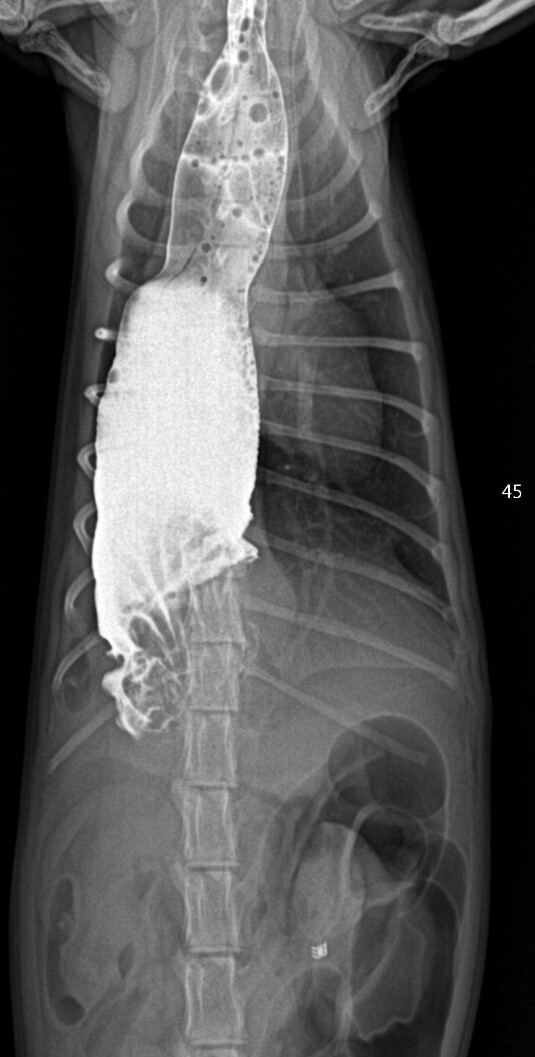

엑스레이 검사에서 식도가 확장되어 있고

위 내에 가스가 많이 차있는 것을 확인할 수

있었습니다. 복강 내 장에서는 이물질도 발

견이 되었습니다.

장폐색을 감별하기 위한 조영 촬영에서

내시경 검사와 마찬가지로 확장된 식도와 식도내강으로 돌출된 위 점막을 확인할 수 있었습니다.

장 내 이물이 발견되기는 하지만 개통에는 문제가

없는 것으로 확인되었습니다.